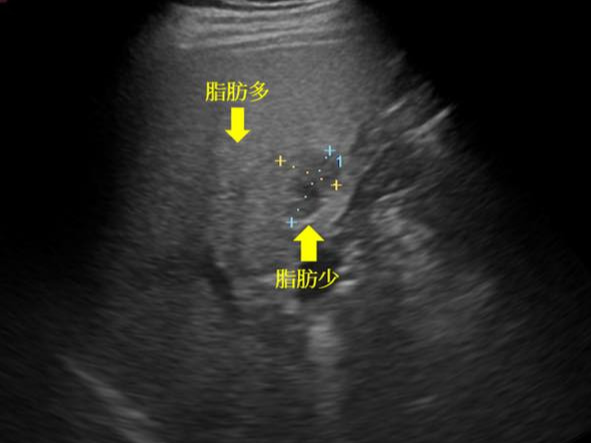

한계

- 종양의 성질(양성/악성) 판단에는 제한

- 비만 환자는 관찰 어려움 가능

- 췌장 전체 확인이 항상 가능하지 않음